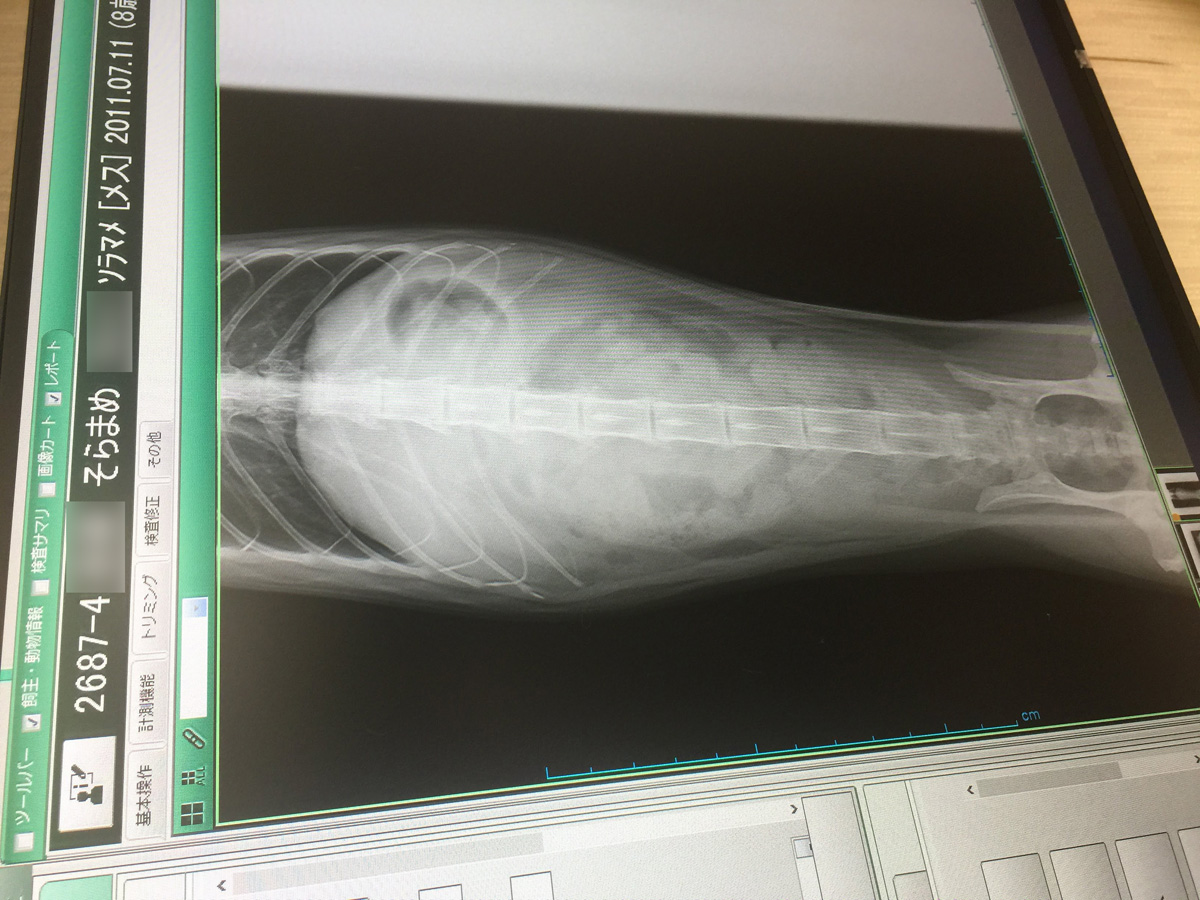

今日は特別に中身を少し公開しちゃうわね これを見たら必ず買わなきゃならないのよ